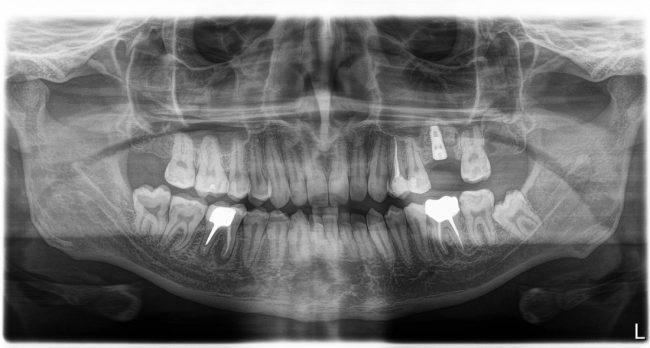

Изначальная клиническая ситуация

Пациенту удалили 26 зуб около двух месяцев назад. Вот компьютерная томография

Подробнее:

В общем, тут нужен синуслифтинг. И, исходя из последних данных об этой операции, 2,6 мм до дна верхнечелюстной полости достаточно, чтобы нормально стабилизировать имплантат, в т. ч. Astra Tech.

26 зуб удалён относительно недавно, поэтому альвеолярный гребень сохранил ширину — это даст нам возможность поставить бескомпромиссно большой по диаметру имплантат — 5.0 мм.

В этой конкретной клинической ситуации первичная стабильность не зависит от длины имплантата, поэтому длину можно выбирать любую. Мы возьмём оптимальную — 9.0 мм. Ибо проще будет с синуслифтингом.